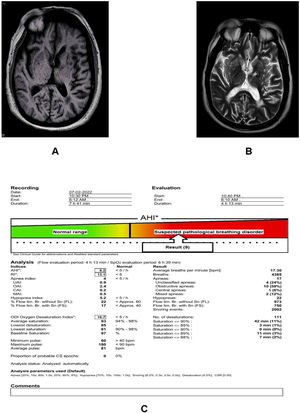

The patient was transferred to the intensive care unit, where intravenous levetiracetam (1 g) was initiated. The basic laboratory parameters were within normal range, including complete blood cell count, cardiac markers, thyroid function test, and renal and liver function parameters, but increased N-Terminal Pro-B-Type Natriuretic Peptide levels (401.4 pg/ml). An electrocardiogram showed non-specific ST changes in V2–V4; a 2D-echocardiographic showed concentric left ventricular hypertrophy with anteroseptal thickening and an ejection fraction of 60% without wall motion abnormalities. An electroencephalogram (EEG) was performed after 6 h following his emergency admission, which was within normal limits without any evidence of focal epileptiform discharges. Brain magnetic resonance imaging (MRI) showed generalized cerebral cortical atrophy with bilateral periventricular white matter subacute ischemic changes and old lacunar infarcts in the bilateral basal ganglia, right thalamus, and bilateral periventricular white matter (Fig. 1A and B). There was no evidence of diffusion restriction and no acute infarct or intracerebral hemorrhage.

Axial-T1- (A) and T2-weighted (B) images reveal generalized cortical atrophy with bilateral periventricular white matter subacute ischemic changes, and old lacunar infarcts in bilateral basal ganglia, right thalamus as well as in periventricular white matter. Fig. C shows alterations in polysomnography parameters.

Epworth sleepiness scale reading was 13/24 (moderate excessive daytime symptoms). Polysomnography evaluation for over 8 h revealed an apnea–hypopnea index of 9.2/h and a respiratory disturbance index of 13.1. The oxygen desaturation index was 16.7/h, with a minimum saturation of 81% (Fig. 1C). Upon discharge, the patient was initiated on oral levetiracetam (500 mg twice daily) for 6 months and maintenance of continuous positive airway pressure during sleep with close follow-up. He was then advised to gradually taper off the levetiracetam and continue only with continuous positive airway pressure. He remained asymptomatic and seizure-free 1 year after discharge, with an improved Epworth sleepiness score.